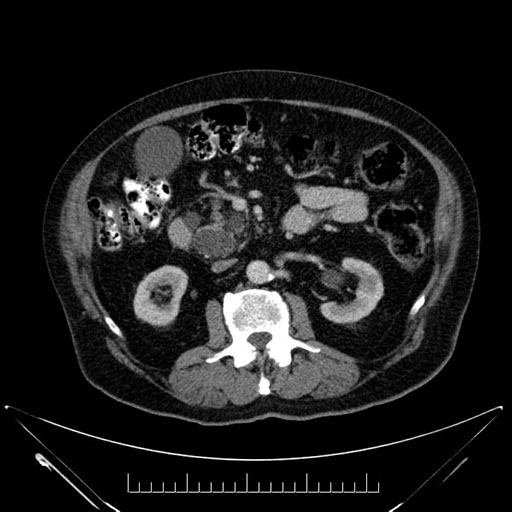

Whipple (pancreaticoduodenectomy) [case 7]

Imaging Analysis

Look through the patient's CT scan to identify any areas of concern for the necessary procedure.

Axial - stented